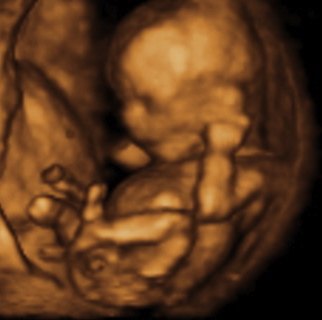

Haha nej, hun sagde også at det var 500% sikkert at det er en dreng!

Det tror jeg på... Hehe... Sådan ser vores billeder fra kønsscanningen ihvertfald ikke ud fra uge 15 - og vi venter os en pige, så det er jo meget heldigt, at de ikke ligner hinanden